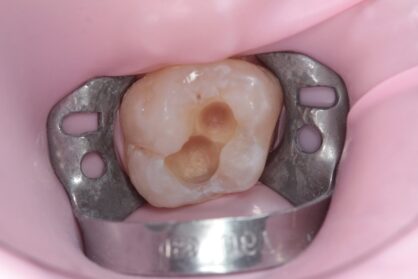

Приклади робіт лікаря-стоматолога

Естетична реставрація. До / після